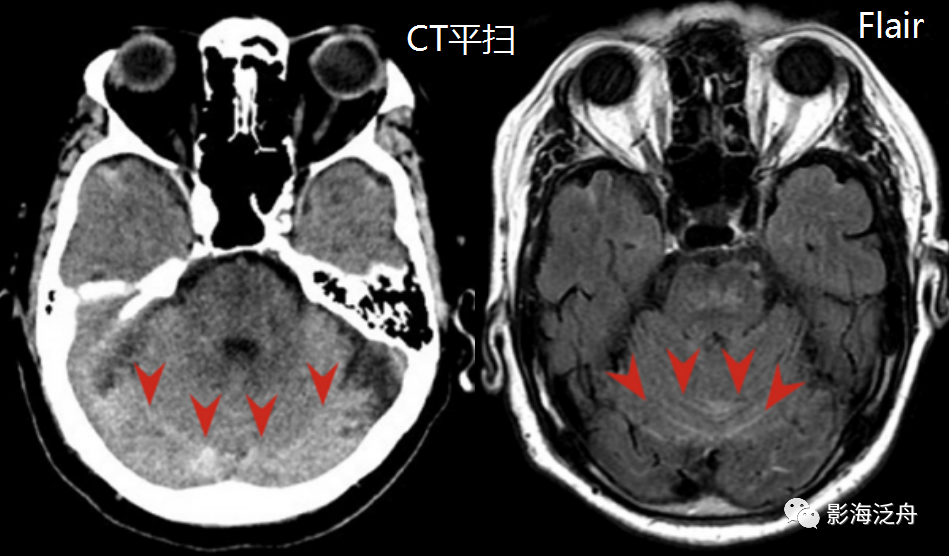

蛛网膜下腔出血的ct平扫表现

蛛网膜下腔出血